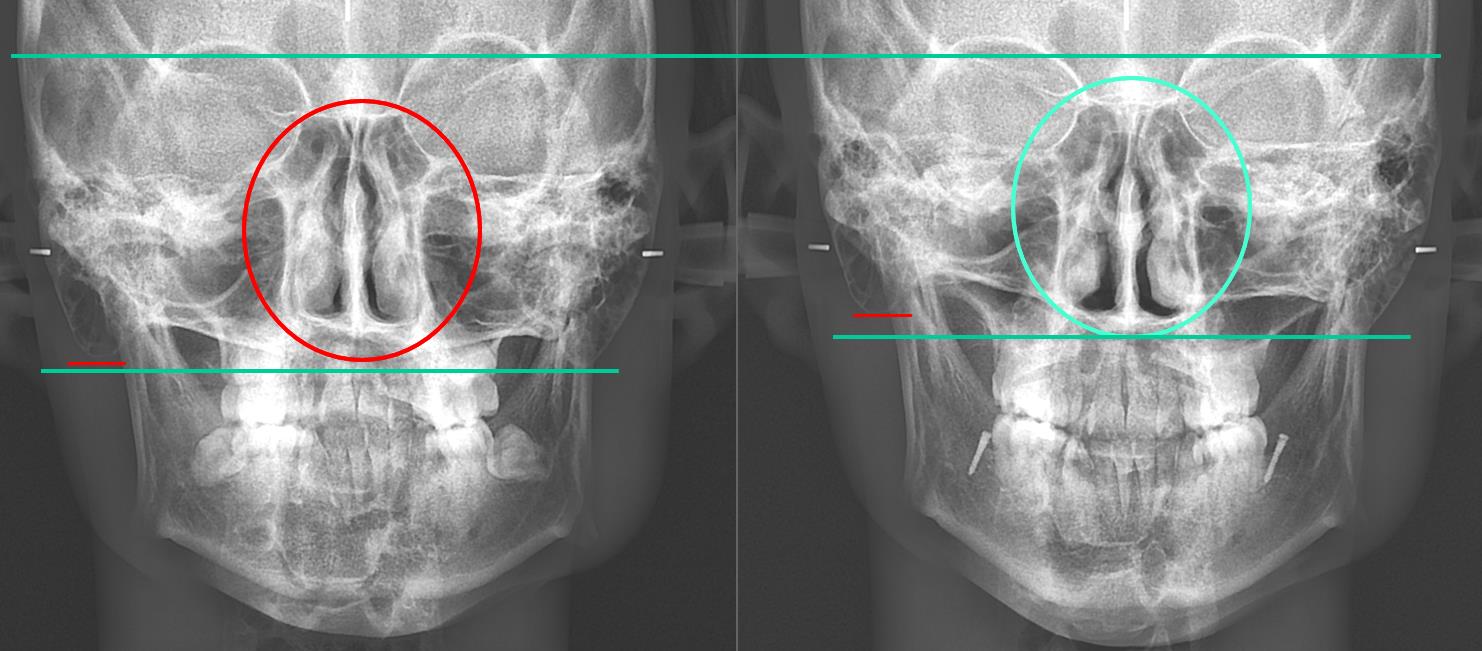

Not long ago, a practicing physician from Prague visited my clinic during orthodontic bracket treatment. She was diagnosed with facial asymmetry and body misalignment, and experienced MCB splint therapy. She was aware that bodily misalignment is related to asymmetry in the facial bones.

Dentistry still remains dominated by the concept of CR (Centric Relation). Many osteopathic physicians have long claimed that the temporal bones move, and treat on that basis, yet the mainstream thinking has not changed. Many dentists still believe that if the mandible (lower jaw) is asymmetric or if the lengths on the right and left differ, surgery is required, and they in fact treat by surgery.